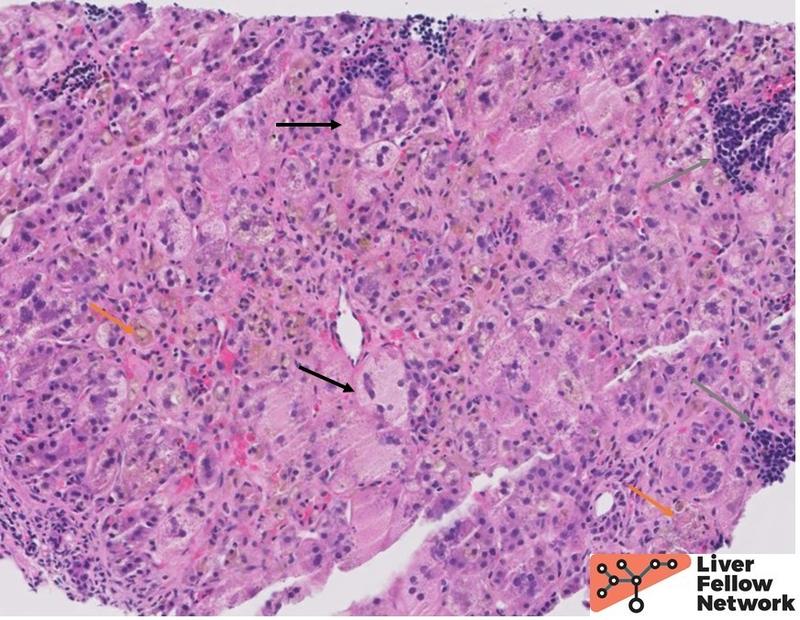

Liver biopsies from neonates will most commonly show a nonspecific neonatal cholestasis pattern secondary to mucus impaction of extrahepatic and intrahepatic bile ducts. The findings include variably prominent cholestasis accompanied by lobular and portal inflammation, giant cell transformation, hepatocyte ballooning and acidophil bodies (Figure 6). Extramedullary hematopoiesis is commonly seen. Neonatal cholestasis has a wide differential, including biliary atresia, infections, drugs and total parenteral nutrition, and a wide array of metabolic disorders such as alpha-1-antitrypsin deficiency, glycogen storage disorders, and progressive familial intrahepatic cholestasis. Consequently, these histologic findings need to be contextualized with respect to the clinical, radiologic, laboratory and genetic findings.

Figure 6. A biopsy from a patient with CF shows inflamed liver parenchyma with prominent hepatocellular and canalicular cholestasis (orange arrow), giant cell transformation and ballooning (black arrow), and patchy extramedullary hematopoiesis (gray arrow).